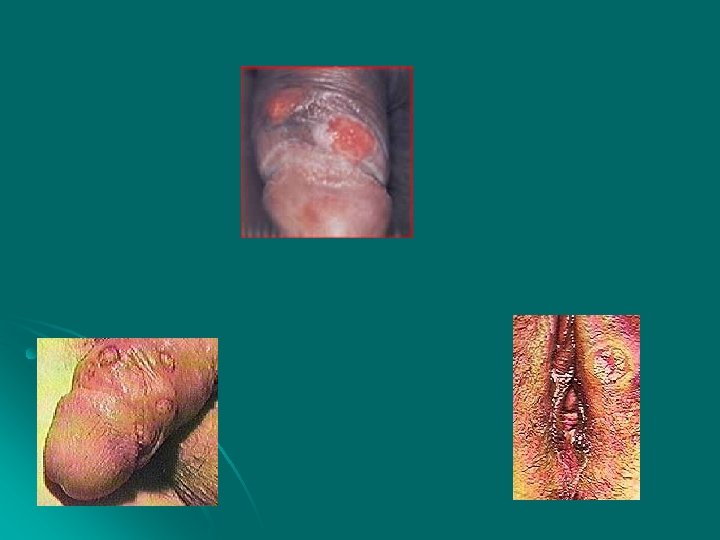

Cancro Mole É causada pela bactéria Hemophilos Ducreyi; l É uma ulceração dolorida e mole; l l Complicações e Conseqüências: Não tem. Tratado adequadamente, tem cura completa.